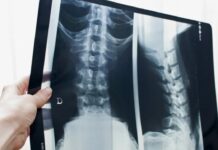

Рентген позвоночника

Рентген позвоночника — это снимок костей спины с помощью низкой дозы рентгеновских лучей. На снимке видно, ровные ли позвонки, целы ли они, не съехали ли относительно друг друга. Видно,...